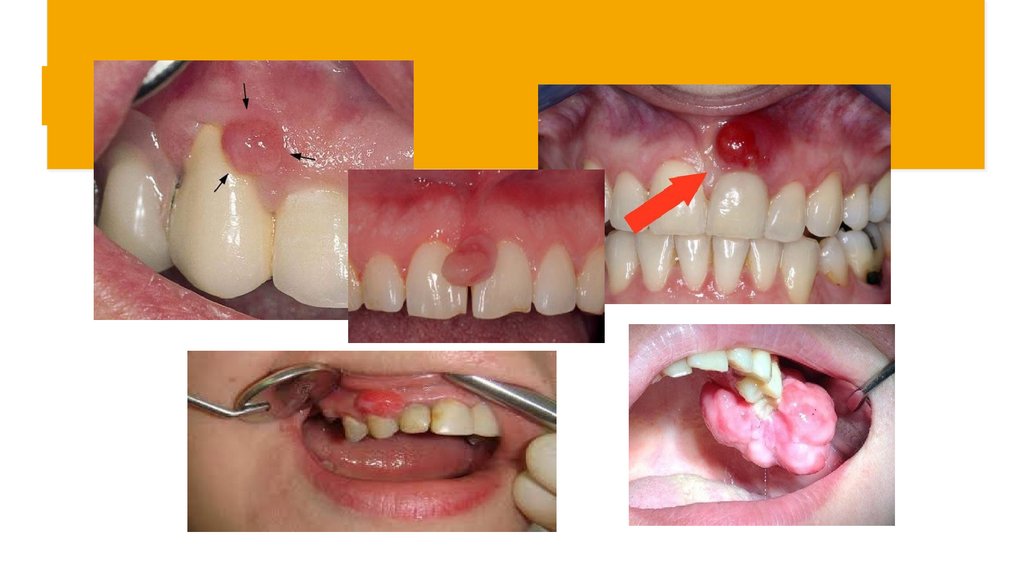

Физикальді тексеру:

Фиброзды түрі:

Қызылиектің вестибулярлық жағында кең, сирек негізде (аяқшамен)

орналасқан және тістерге жақын орналасқан дөңгелек немесе дұрыс

емес пішіннің қалыптасуы тіс аралық арқылы оральды жағына таралуы

мүмкін;

· Бозғылт қызғылт түсті шырышты қабықпен жабылған, беті тегіс немесе

кедір-бұдыр, тығыз эластикалық консистенциялы, ауыртпалықсыз,

қанамайды.

47.

Ангиоматозды түрі:

· Тістің мойнында орналасқан;

· Кішкене кедір бұдырлы , сирек тегіс бет, ашық қызыл түсті

цианотикалық реңкпен, салыстырмалы түрде жұмсақ консистенциямен.

· Жеңіл жарақат кезінде де қан кетеді.

48.

Перифериялық алып жасуша формасы:

· Дөңгелек немесе сопақ пішінді ауыру сезімінсіз түзілім ;

· Кедір-бұдырлы бет, жұмсақ немесе тығыз серпімді консистенциялы, көкшіл-күлгін

түсті.

· Жақтың альвеолярлы бөлігінде орналасқан, қанайды.

· Эпулис бекітілген тістер ығысып, босатылады.